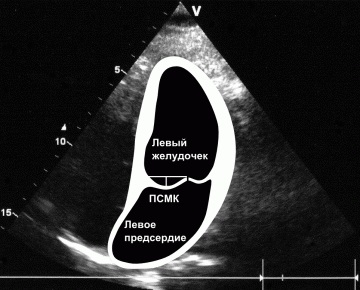

Itt egy tipikus kép egy négykamrás szakaszról, amely szerint az oroszországi echokardiográfusok többsége egyértelműen előidézi a prolapsus MK-t:

Ha a bal szívét vázolja, az orosz doktor-echokardiográfus szokásos akciói a következők:

Tartott egy egyenes vonal a bázis a szélén a elülső betegtájékoztató a mitrális billentyű (PSMK), majd a mért milliméterben elhajlást központ és abban következtetést a jelenléte a beteg elülső betegtájékoztatót előesés MK és annak mértékét.

Süllyedés, vagy megereszkedett, az egyik vagy mindkét mitrális szisztolés fázis alatt tartják igaz csak akkor, ha be van jegyezve két echokardiográfiás helyzetben :. Apical négy kamra és parasternalis a hosszanti tengelye mentén a bal kamra „End quote.

Itt van a kutya eltemetve, kedves kollégák, echokardiográfusok. A parasternal helyzetben az úgynevezett "prolapsusok" 99% -a azonnal levágódik.

Gyakran láttál ilyen képet egy parasternal helyzetben? Nem.